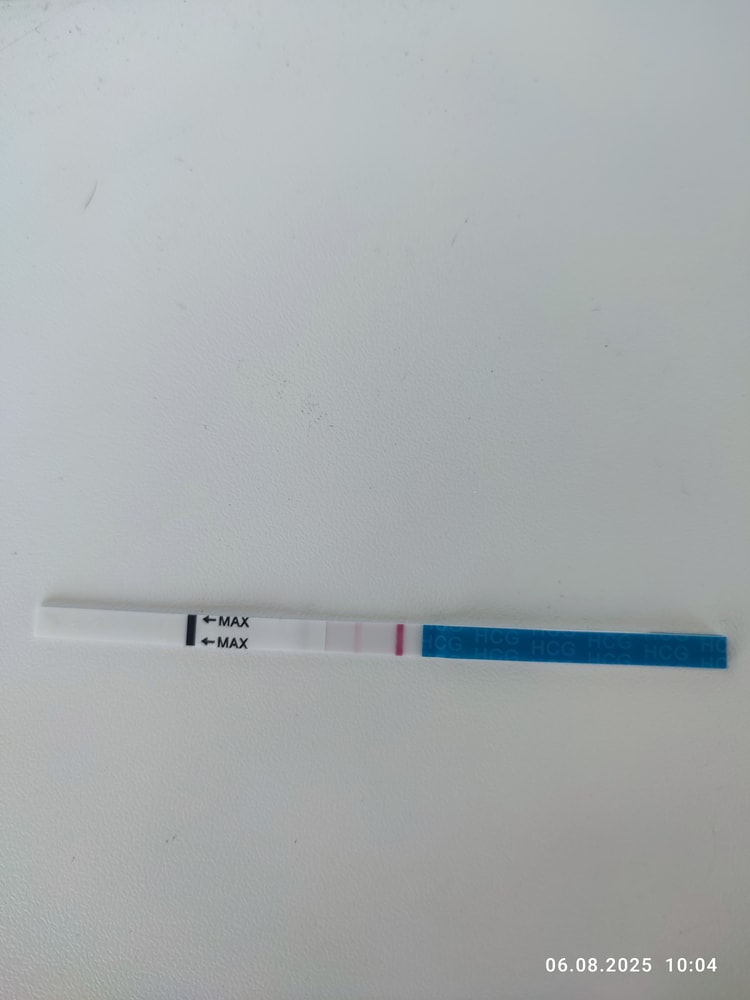

Первые два мама чек

Третий эвик

Мне кажется у эвика что-то есть, но надо повторить однозначтно

Мария Кот, я тоже на эвике вижу, но надо смотреть дальше